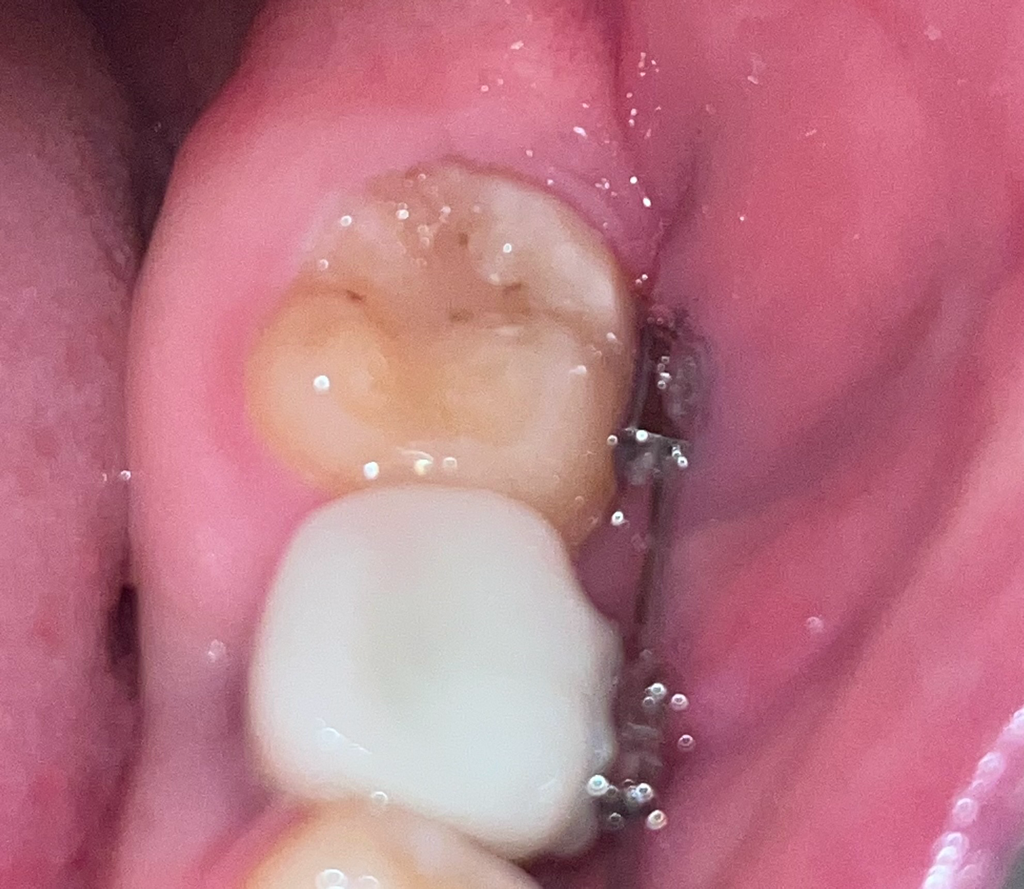

어금니에 검은 점이 생겼는데 충치인가요?

제목 그대로 검은? 갈색? 점이 생겼고 몇개월간 있었습니다. 큰변화도 없었고 시리다거나 음식을 먹을때 아픈느낌은 없어서 이게 충치인지 아닌지 모르겠어서 글 올립니다. 저는 현재 교정치료와 임플란트를 받고 있는 상태입니다. 잇몸이 조금 부어오른것은 아마 교정때문이라고 생각되긴 합니다만 전문가분들의 의견이 필요합니다. 답 주시면 감사하겠습니다.

초기충치이거나 이전 떼운재료의 착색 또는 변색양상으로 생각됩니다 충치라하더라도 아직까지 충치치료가 필요한 상황으로 보이지는 않습니다

충치보다는 변색이 되었을 것으로 보이지만 충치 가능성도 있습니다. 치과 가보시는 게 좋습니다.

사진에 보이는건 예전에 치료를 한부분이 시간이 지나면서 미세틈이 생기고 착색 및 2차 충치가 조금 생긴거 같습니다

차근으로는 정확하게 판단하기 힘들어 보이지만 이전에 충전을 했던 레진 주위로 착색이 생긴 것으로 보입니다. 크게 문제가 되진 않을 것으로 보이나 정확한 확인을 위해서 치과에서 진료를 받아보세요.

현재 사진상 충치로 보이며, 방치시에 충치가 더 진행될수 있기에 치과에 방문하여 진료를 받고 충치 치료를 받길 권합니다.